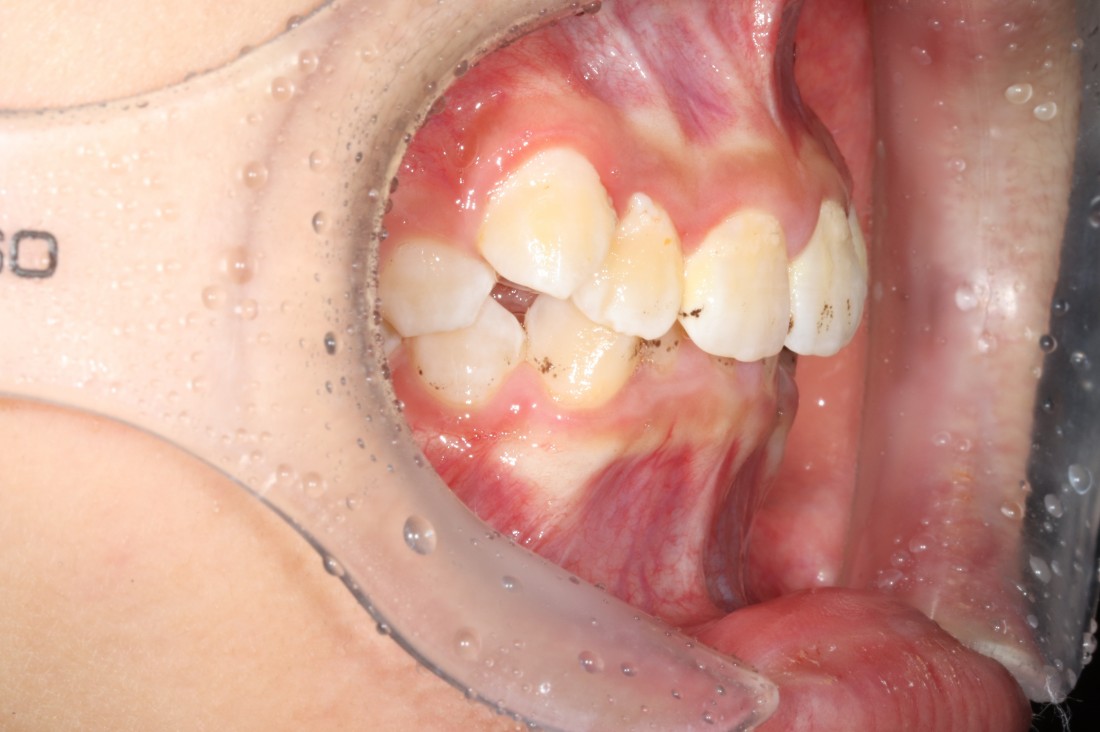

발치, 충치치료,

필요한 경우 임플란트 까지

모두 분과별 담당 전문의가 합니다.

전문의 대표원장

동시 협진 시스템으로

최상의 치료계획을

세우고 있습니다.